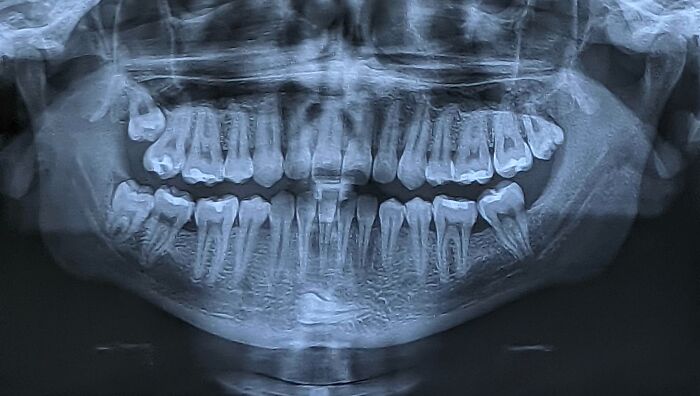

#1 Röntgen gymnastky pri predvádzaní triku